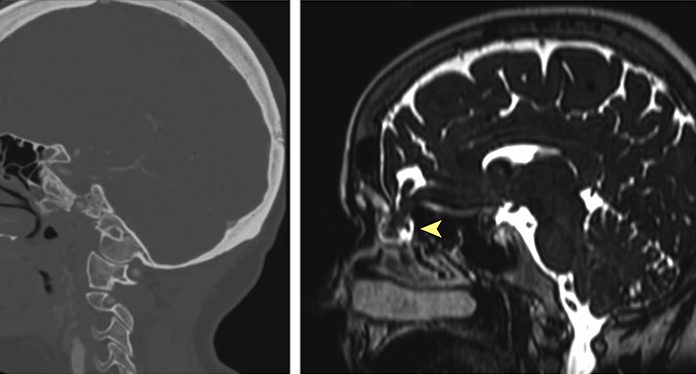

Test za koronavirus predrl možgansko pregrado in puščati je začela možganska tekočina

Predrtje možganske pregrade in puščanje cerebrospinalne tekočine po korona testu pokazalo, da je test lahko tudi smrtno nevaren.